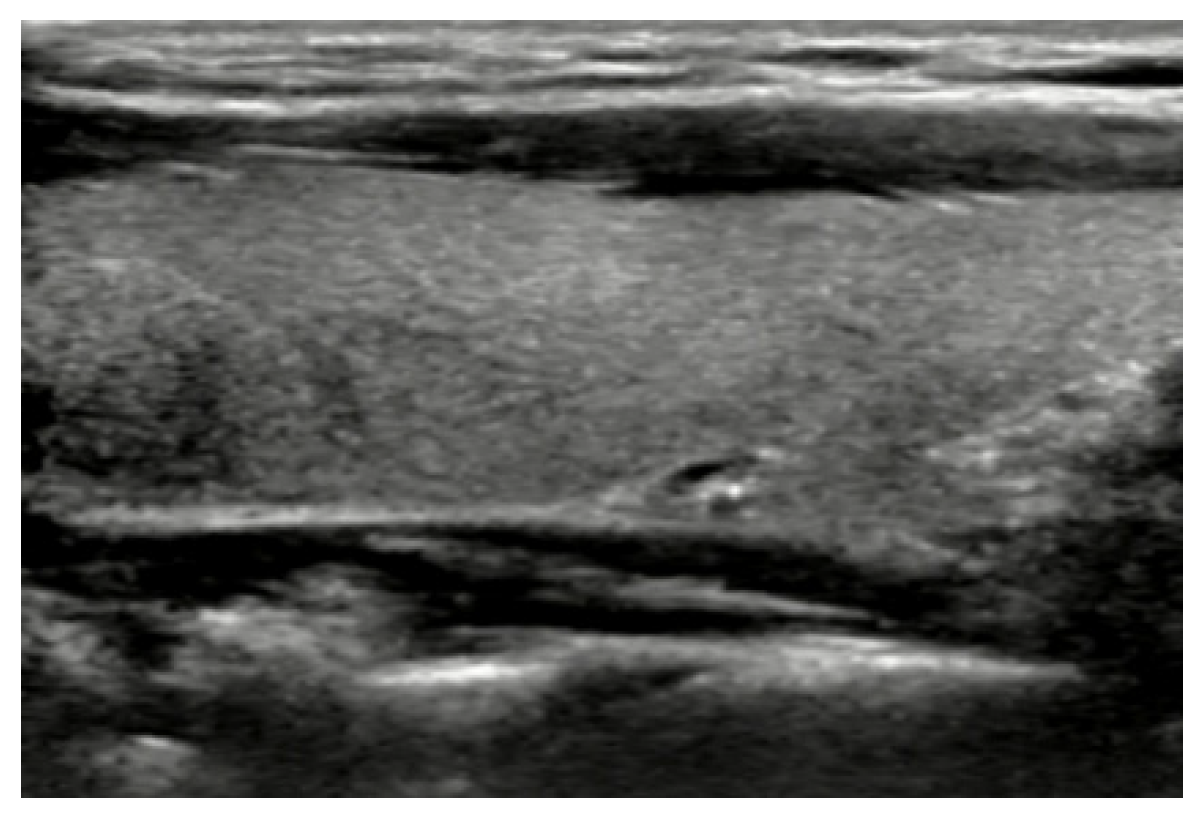

A longitudinal B-mode image of the normal thyroid was shown in Figure 1 where homogeneous isoechoic structure and nearly regular well-defined margins could be found in the image. Based on the echogenicity change in B-mode ultrasonography, the pathological change of thyroid gland was determined in clinics. Moreover, thyroid nodules could be classified by boundaries of ROI and texture features in images. Figure 2 shows distinct ultrasound features and accordingly pathologic findings comparing between benign and malignant lesions. A thyroid adenoma (Figure 2a) with ultrasonographic features of hyperechoic echogenicity, no calcification, and wider shape, was benign, finally proven by FNA findings. Its pathologic result showed that the follicular cavity is filled with gelatinous material, and that a papillary structure is partially visible (Figure 2c). On the contrary, hypoechoic echogenicity, microcalcification, and taller shape demonstrated a malignant papillary thyroid carcinoma (Figure 2b), with complex branched papillaries containing fibrous vascular cores (Figure 2d).

Figure 1.

A longitudinal B-mode image of the normal thyroid.

Figure 2.

B-mode US images and corresponding FNAs of benign and malignant thyroid nodules: (a) B-mode image of benign thyroid nodule; (b) B-mode image of malignant thyroid nodule; (c) FNA smears of benign thyroid nodule; and (d) FNA smears of malignant thyroid nodule.